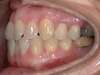

Chevauchement sévère. Traitement multibague sans extraction.

Avant

Après